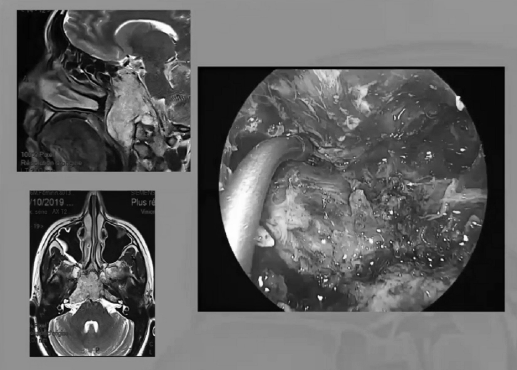

▼这个病例,它影响了颈1颈2.然后没有侵袭到硬膜内,我就不考虑用内镜了。考虑到脑脊液的释放等问题,这里我用了后外侧的一个入路。利用45度的内镜往上看,往上磨除岩骨的后方,可以一直暴露颈内动脉的岩骨段,然后海绵窦段。然后在显微镜下我们可以进行双手的操作,神经外科医生就比较熟悉的了。我们在做手术切除肿瘤切完了之后,还要进行固定。